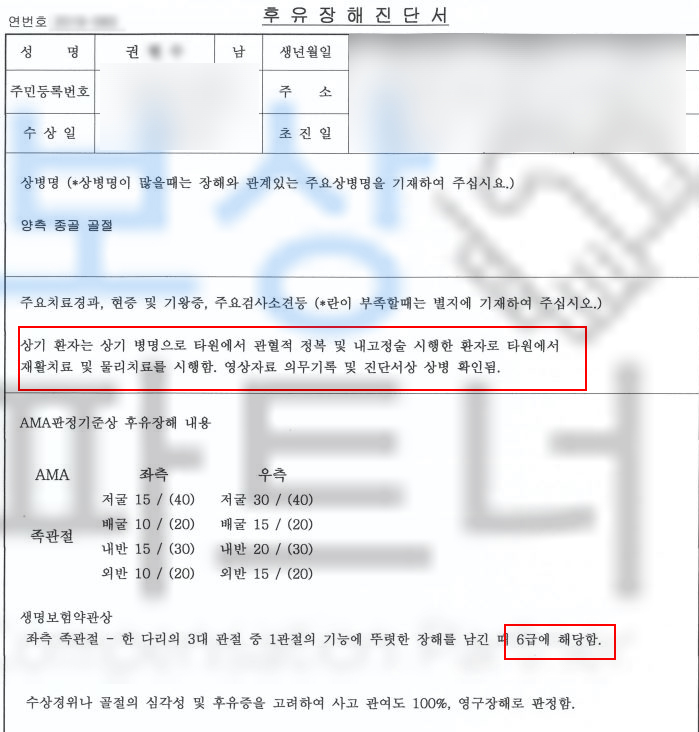

급수 보험도 있으셨습니다. 저희는 올바르고 분명한 보험금을 위해 공신력 있는 대학병원의 전문의로부터 후유 장해 진단을 받았고, 그 결과

권@@님은 무려 AMA 약관상

좌측은 뚜렷한 기능 장해 10%

우측은 약간의 기능 장해 5%

생명보험약관상은

우측은 장해에 해당이 안 되고

좌측은 뚜렷한 장해 6급에

해당되었습니다.